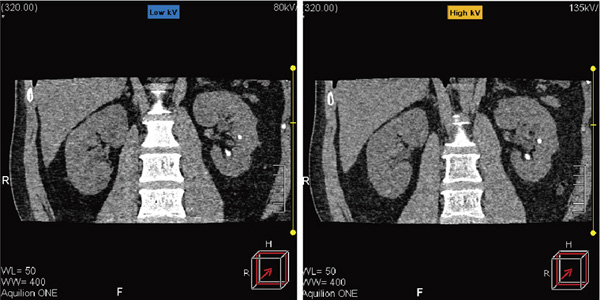

(2)管電流の設定が自由(図4)

デュアルエネルギーによる解析は,CT値の比較となるため,2つの管電圧の画像のSD値がそろっていることが望ましい。DE-Volでは管電流の設定に自由度があり,管電圧に応じて適切な管電流を用いることができる。管電流はメニューから選択,または,数値入力により簡単に設定することができる。

また,管電流自動設定機能である“Real EC”を用いることにより,2つの管電圧それぞれで指定したSD値を得るための管電流を自動的に設定することも可能である。

図4 撮影画像例